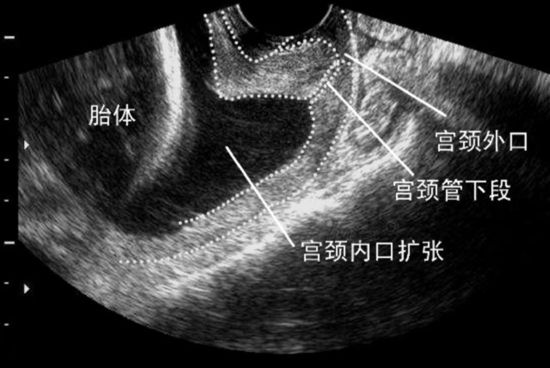

- 宫颈长度:孕早期宫颈长度 ≤ 3.0 cm 提示可能存在问题;≤ 2.0 cm 则可基本确定诊断。

- 宫颈内口扩张:孕早期宫颈内口宽度 ≥ 1.5 cm,或孕中期内口扩大 ≥ 2.0 cm,都需要高度警惕。

- 特殊形态:如果超声发现羊膜囊向宫颈管内突出,甚至部分胎囊膨入,是宫颈功能不全的典型表现。